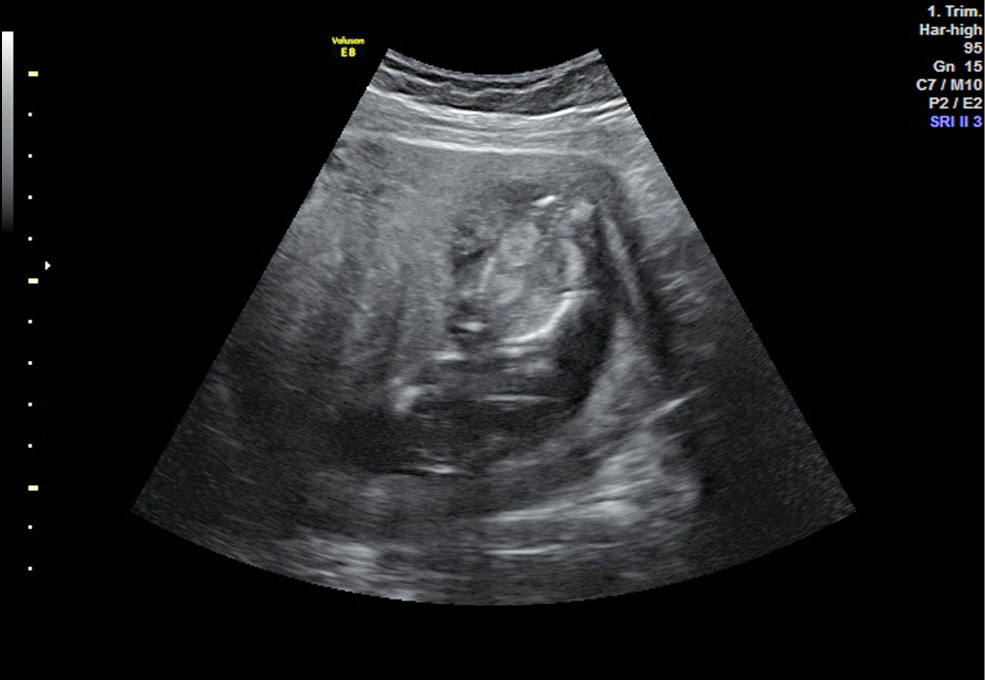

Рис. 2. Эхограмма 2D. Беременность 17 нед. Подтвержденный врожденный порок развития плода. Кистозная дисплазия почек у плода. Маловодие

Fig. 2. Echogram 2D. Pregnancy 17 weeks. Confirmed congenital malformation of the fetus. Cystic dysplasia of the kidneys in the fetus. Malnutrition